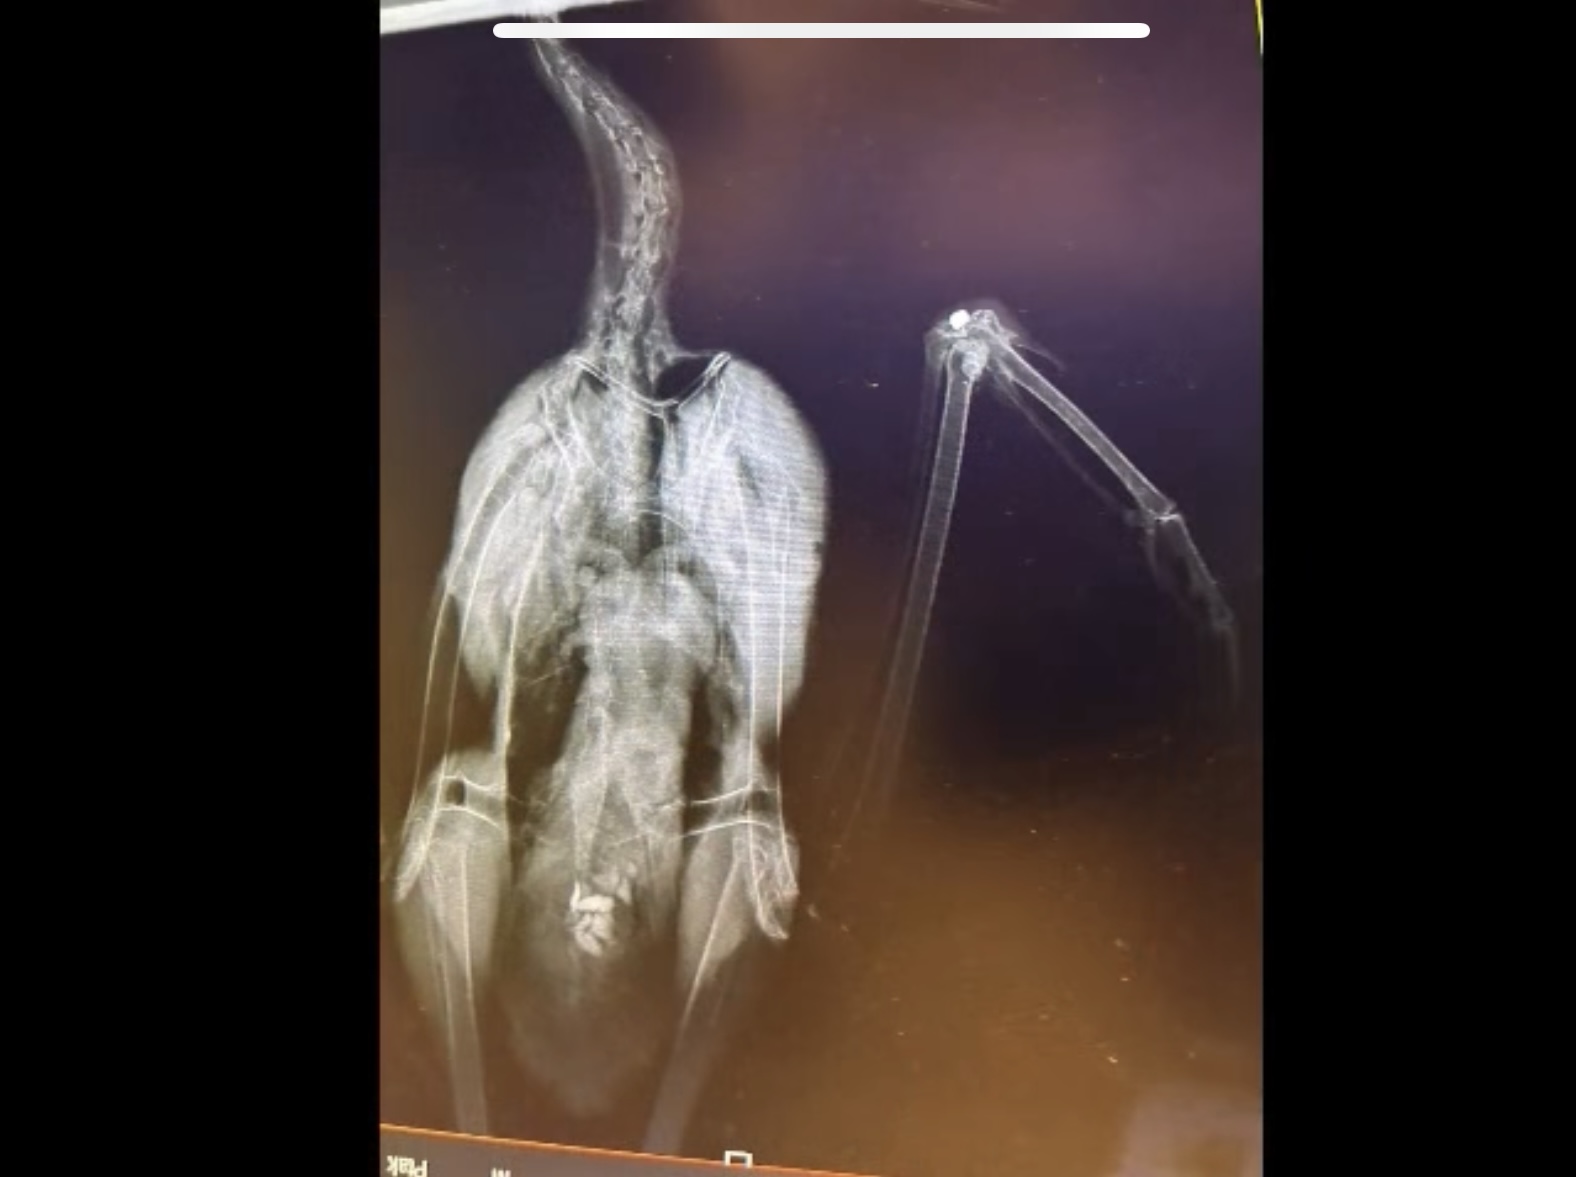

Zaledwie trzy dni później jednego z bocianów znalazł nieopodal azylu, miał niesprawne skrzydło. Okazało się, że tkwi w nim śrut...

Ktoś do niego strzelał. Dach, na którym bocian usiadł, był dla niego wyrocznią... Bocian, który spędził zimę w naszym ośrodku, codziennie się nim opiekowaliśmy, a zima była naprawdę bardzo trudna w tym roku.

Staraliśmy się, stawaliśmy na rzęsach, żeby te zwierzęta, które sa u nas, były jak najlepiej zaopiekowane. I niedawno 20 takich zwierząt wypuściliśmy na wolność. Ten biedaczek jest już po operacji. Ma wyciągnięty śrut. Sprawa z automatu jest oczywiście zgłoszona na policję - mówi w nagraniu na swoim profilu Piotr Nadolski z Fundacji Skrzydła Lasu.